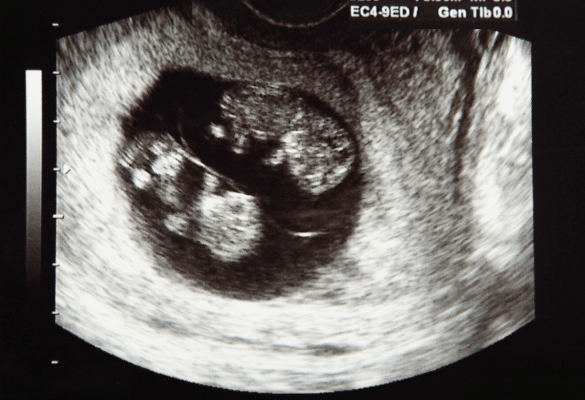

Le seul moyen fiable de savoir si l’on attend des jumeaux reste l’échographie du premier trimestre. Elle permet de compter le nombre d’embryons et de déterminer le type de grossesse (bichoriale, monochoriale…).

Je voyais mes filles presque chaque semaine à l’échographie.

Dans son cas, Léa a vécu une grossesse monochoriale biamniotique : un placenta commun, deux poches amniotiques. Dans certaines grossesses monochoriales comme la sienne, les médecins surveillent le risque rare de syndrome transfuseur-transfusé, où la circulation sanguine entre les deux bébés peut devenir déséquilibrée.

Selon la Haute Autorité de Santé (HAS), ce phénomène spécifique aux grossesses partageant un même placenta justifie un suivi échographique plus rapproché (Recommandations professionnelles, 2019). Heureusement, tout s’est bien passé pour les jumelles de Léa.